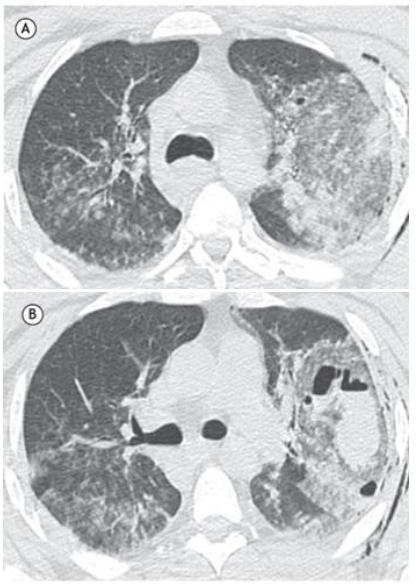

Homem de 38 anos, sem comorbidades, deu entrada no pronto-socorro após acidente de moto, queixando-se de dor torácica, tosse e hemoptise.

O paciente realizou tomografia computadorizada como parte da rotina diagnóstica.

O resultado foi:

Em relação ao exame apresentado, assinale a afirmativa correta.